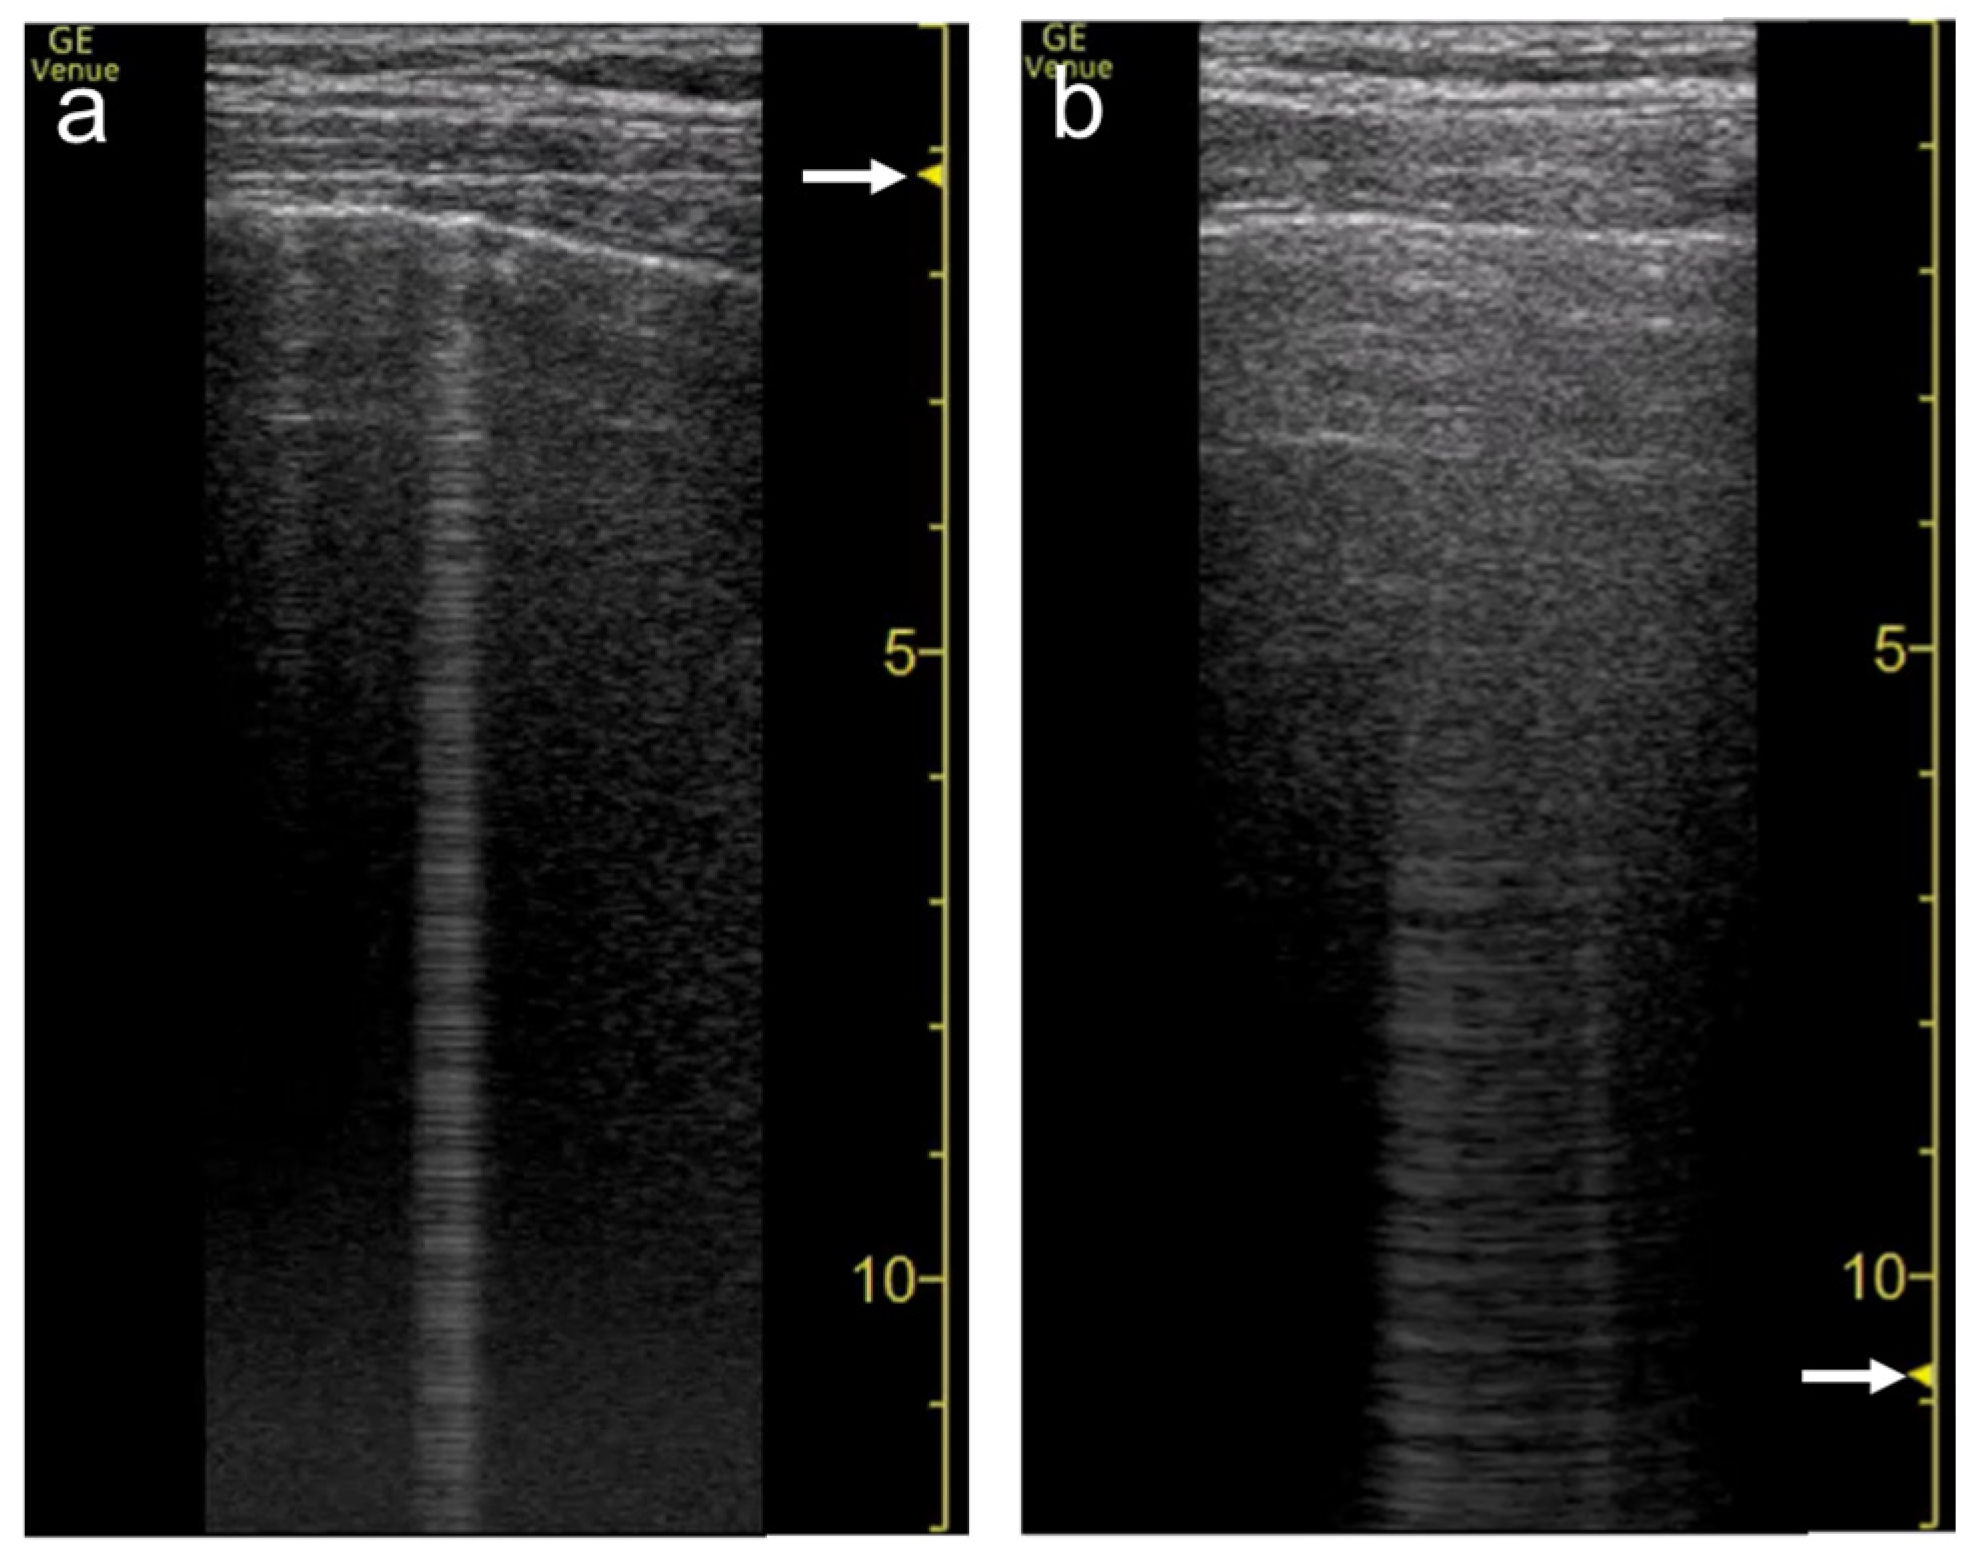

3.3. Frequency